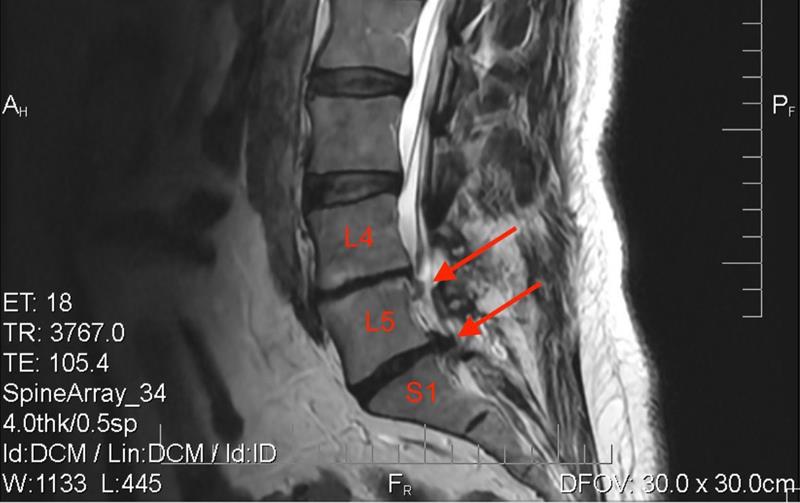

Tại Bệnh viện Hoàn Mỹ ITO Đồng Nai, các bác sĩ chẩn đoán bệnh nhân bị thoát vị đĩa đệm cột sống thắt lưng L4-L5 và L5-S1 tái phát gây chèn ép rễ thần kinh. Điều này khiến tình trạng đau nhức dữ dội ở vùng thắt lưng và lan xuống chân trái, gây tê bì, yếu cơ, đi lại khó khăn, chân trái teo rõ.

Hình ảnh thoát vị đĩa đệm của bệnh nhân trên phim chụp